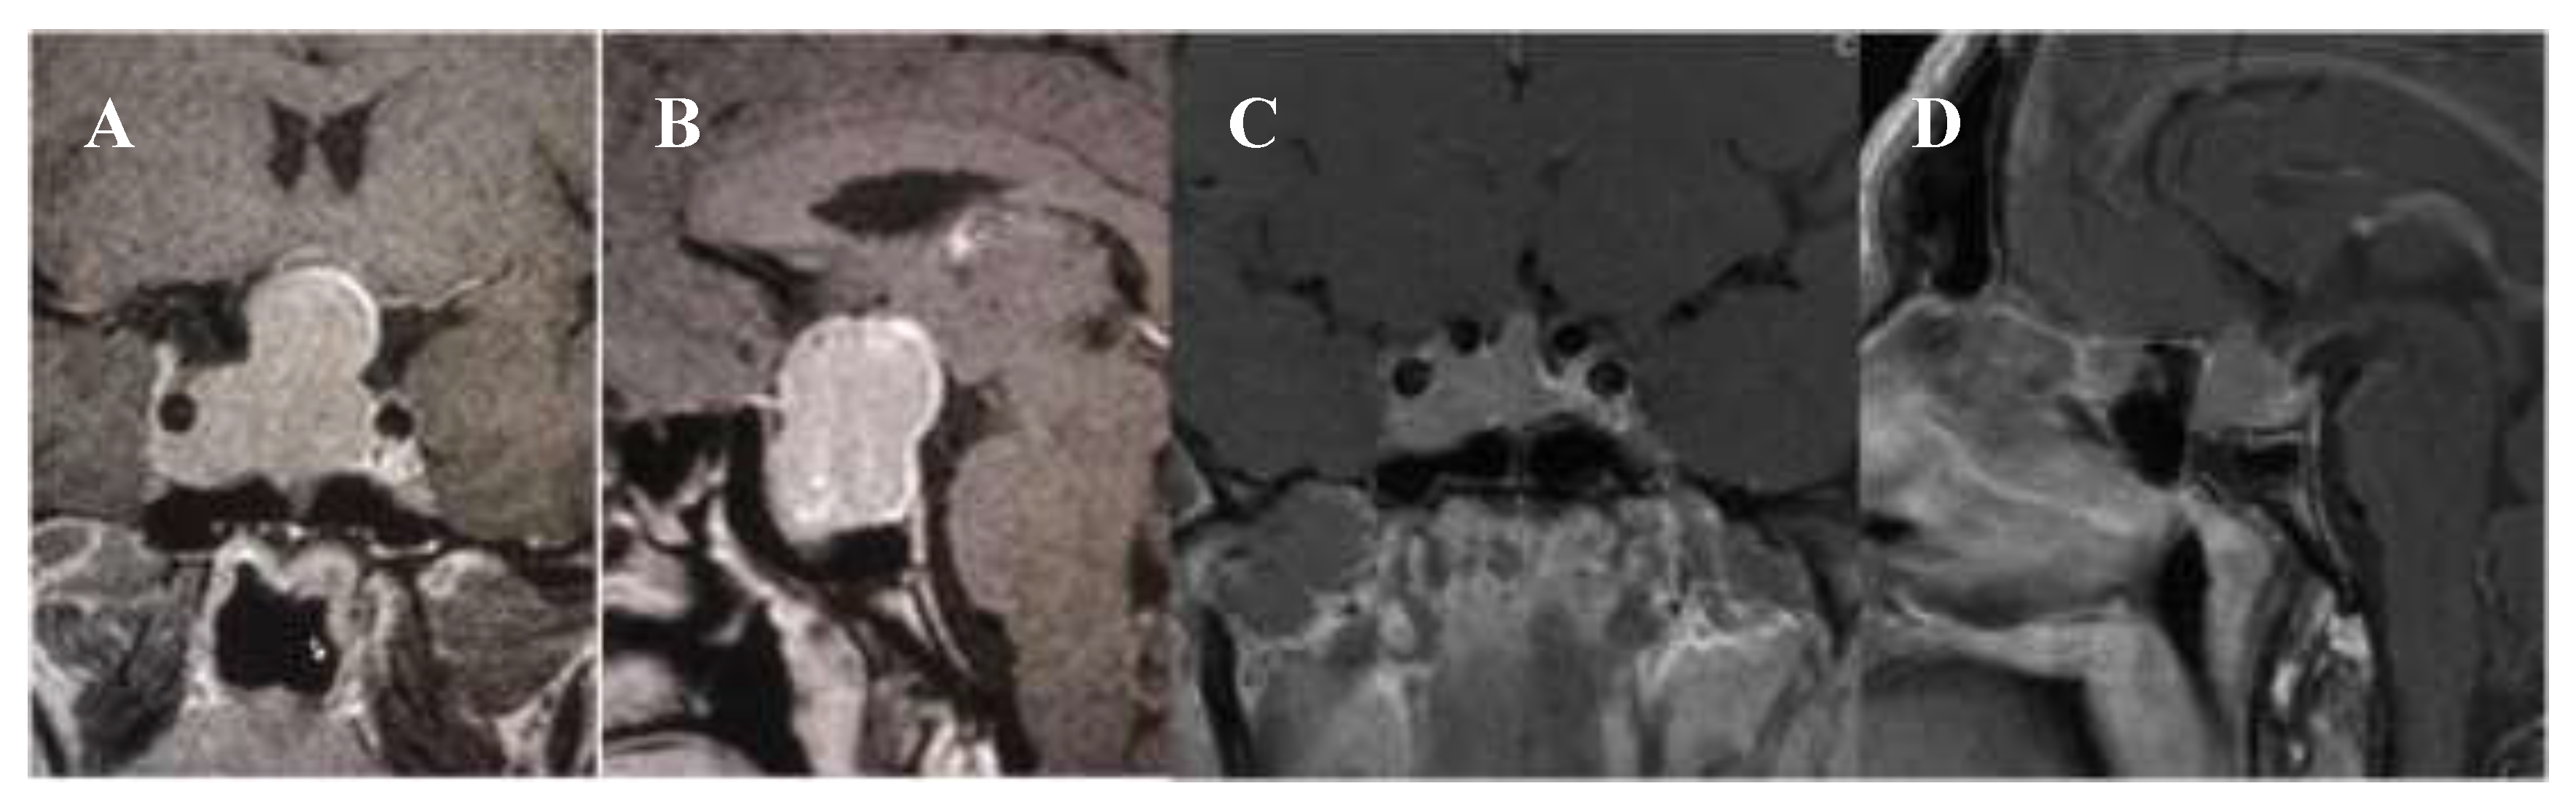

2. Case Presentation